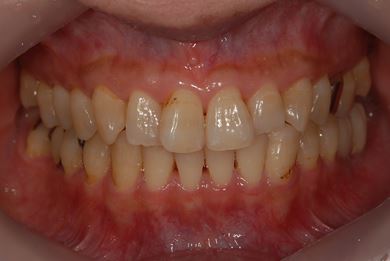

インプラントの症例写真 IMPLANT

インプラント治療

| 性別/年齢 | 女性 / 46歳 | ||||||||||||||||||||||||||||||||

| 主訴 | 左奥歯のインプラント治療を希望。 | ||||||||||||||||||||||||||||||||

| 治療方針 | 左下奥、欠損部分をインプラント治療にて、機能的・審美的回復を行う。 | ||||||||||||||||||||||||||||||||

| 治療内容 | インプラント2本、ハイブリッドセラミッククラウン2本 | ||||||||||||||||||||||||||||||||

| 総治療費 | 399,000円 | ||||||||||||||||||||||||||||||||

| 治療期間 | 5ヶ月 |